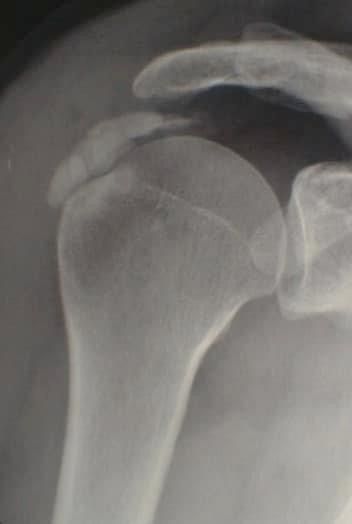

La Dottoressa Morgano Maria Chiara si è laureata in Medicina e Chirurgia presso l’università degli studi di Palermo con 110/110 e Lode. Ha conseguito la specializzazione in Radiologia col massimo dei voti e Lode presso l’università degli studi dell'Insubria. Durante il percorso di specializzazione presso l'Ospedale di Varese "Ospedale di Circolo e Fondazione Macchi", ha acquisito buone competenze diagnostiche come radiologo generale sull'utilizzo di varie metodiche di imaging (RX, ecografia, Tomografia Computerizzata, RM), ma ha dedicato gran parte della sua formazione alla Radiologia Muscolo-scheletrica Diagnostica ed Interventistica, maturando esperienze e competenze nel trattamento ecoguidato di patologie muscolo-tendinee. Ha completato il suo percorso di specializzazione presso "Columbus Clinic Center" a Milano, dove ha avuto la possibilità di seguire un vasto numero di Risonanze su atleti e sportivi come ad esempio giocatori di A.C. Milan, acquisendo competenze specialistiche nell’ambito delle patologie sportive. Ha lavorato come libera professionista presso Vari studi privati nella città di Siena ove praticava l'ossigeno-ozonoterapia sulla colonna per poi lavorare come dirigente medico presso l'Azienda Ospedaliera di Busto Arsizio. Ha lavorato presso l'Ospedale di Carate Brianza, dove ha avviato l'ambulatorio di ecografie muscolo-tendinee ed infiltrazioni eco-guidate. Da gennaio 2026 lavora presso l’ospedale IRCCS Multimedica di Sesto S. Giovanni dove esegue ecografie ed infiltrazioni ecoguidate. Svolge inoltre attività libero-professionale in ambito di Medicina Estetica, integrando alla visita clinica una valutazione ecografica accurata del volto. Questo le permette di utilizzare le competenze ecografiche maturate nella radiologia anche nei trattamenti estetici, al fine di ridurre il rischio di complicanze, indirizzare con precisione l’area da trattare e gestire in modo più efficace eventuali complicanze.

Foto e video